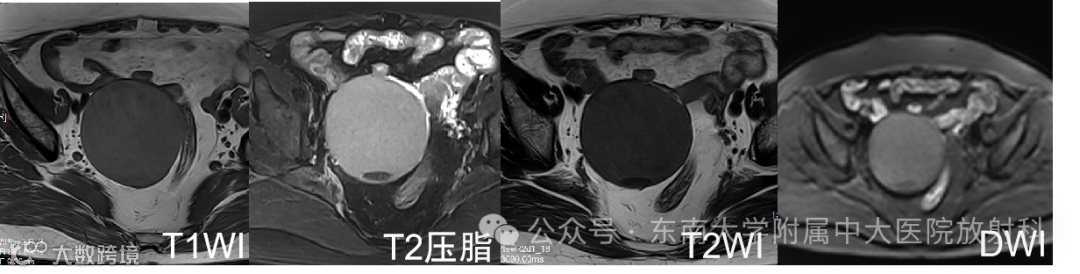

女 ,69岁 主诉:发现盆腔包块 1 天

现病史:患者53岁自然绝经,无异常阴道流血、流液。1 天前于我院体检发现盆腔包块,查阴道B超:右侧附件区见一囊性包块,大小:8.2cm×6.7cm×7.6cm,外形尚规则,界尚清,壁厚 0.24cm,内部透声差,见散在小颗粒样中高回声,见数条分隔带,CDFI:囊壁上见少量血流信号

有尿频尿急,无腹痛腹胀,无腰酸。实验室检查无异常